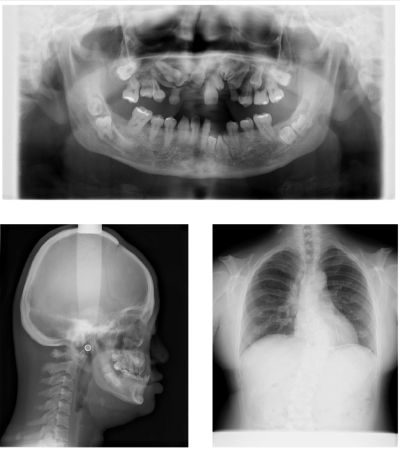

36歳の男性。咀嚼困難を主訴として来院した。幼少時から遺伝疾患を指摘されているという。低身長と歯列不正が認められる。初診時のエックス線写真を示す。

考えられるのはどれか。1つ選べ。

a. 大理石骨病

b. Marfan症候群

c. Gardner症候群

d. 基底細胞母斑症候群

e. 鎖骨頭蓋骨異形成症